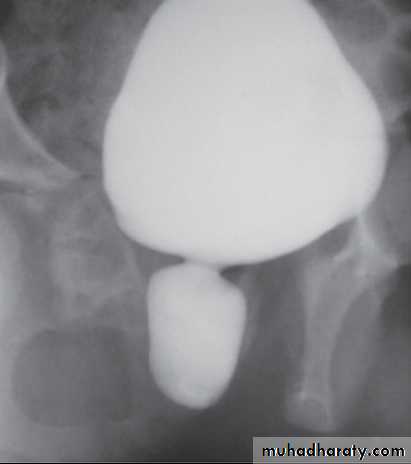

Voiding cystourethrogram :dilated post. Urethra ,valve leaflet , thick Bladder neck